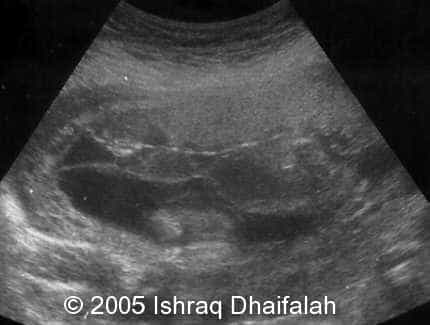

Oligohydramnios of fetus B:

image2